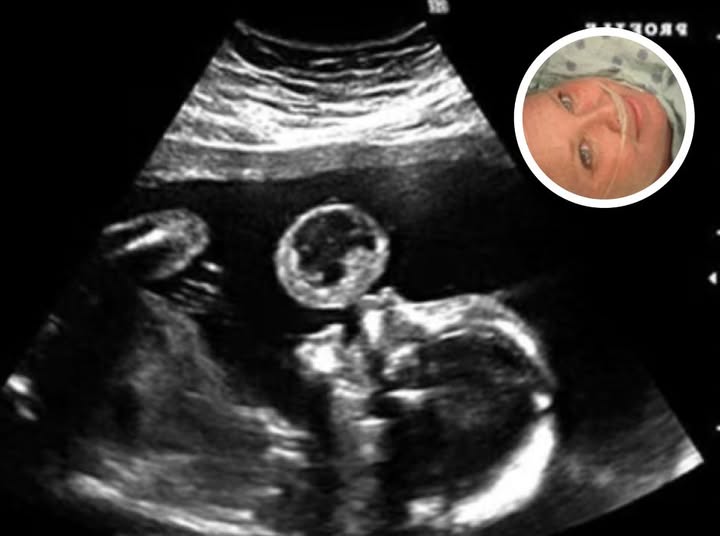

Mom Thinks Her Baby Is Blowing Bubble In Ultrasound, Then Doctors Discover What It Really Is

Tammy Gonzalez, a Miami mother, went in for what she expected to be a routine…